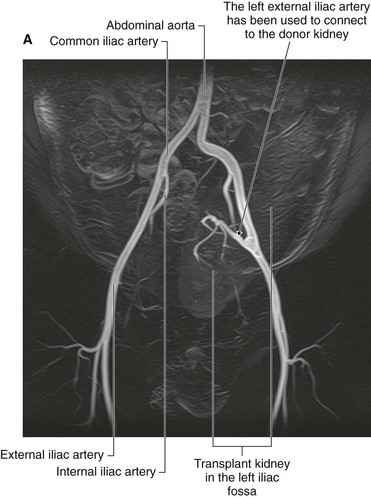

Kidney transplant

Kidney transplantation began in the United States in the 1950s. Since the first transplant, the major problem for kidney transplantation has been tissue rejection. A number of years have passed since this initial procedure and there have been significant breakthroughs in transplant rejection medicine. Renal transplantation is now a common procedure undertaken in patients with end stage renal failure.

Transplant kidneys are obtained from either living or deceased donors. The living donors are carefully assessed, because harvesting a kidney from a normal healthy individual, even with modern day medicine, carries a small risk.

Deceased kidney donors are brain dead or have suffered cardiac death. The donor kidney is harvested with a small cuff of aortic and venous tissue. The ureter is also harvested.

An ideal place to situate the transplant kidney is in the left or the right iliac fossa (Fig. 4.146). A curvilinear incision is made paralleling the iliac crest and pubic symphysis. The external oblique muscle, internal oblique muscle, transverse abdominis muscle, and transversalis fascia are divided. The surgeon identifies the parietal peritoneum but does not enter the peritoneal cavity. The parietal peritoneum is medially retracted to reveal the external iliac artery, external iliac vein, and the bladder. In some instances the internal iliac artery of the recipient is mobilized and anastomosed directly as an end-to-end procedure onto the renal artery of the donor kidney. Similarly the internal iliac vein is anastomosed to the donor vein. In the presence of a small aortic cuff of tissue the donor artery is anastomosed to the recipient external iliac artery and similarly for the venous anastomosis. The ureter is easily tunneled obliquely through the bladder wall with a straightforward anastomosis.

image image

Fig. 4.146 Kidney transplant. A. This image demonstrates an MR angiogram of the bifurcation of the aorta. Attaching to the left external iliac artery is the donor artery for a kidney that has been transplanted into the left iliac fossa. B. Abdominal computed tomogram, in the axial plane, showing the transplanted kidney in the left iliac fossa.

The left and right iliac fossae are ideal locations for the transplant kidney, because a new space can be created without compromise to other structures. The great advantage of this procedure is the proximity to the anterior abdominal wall, which permits easy ultrasound visualization of the kidney and permits Doppler vascular assessment. Furthermore, in this position biopsies are easily obtained. The extraperitoneal approach enables patients to make a swift recovery.